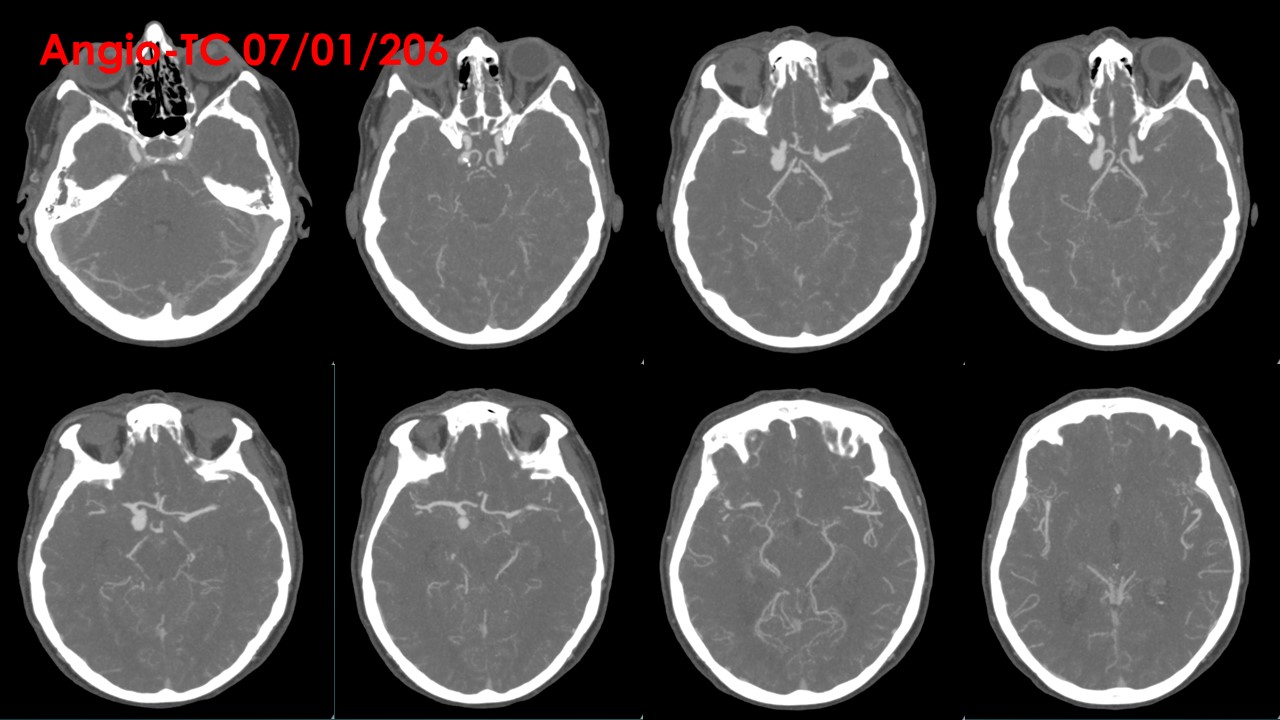

TC CRANEAL SIN CONTRASTE

Extensa hemorragia subaracnoidea aguda con afectación de las cisternas peritronculares, cisura Silviana bilateral, de predomino derecho y los surcos de la convexidad predominantemente derechos. Se asocia a contaminación hemática tetraventricular con leve aumento de tamaño del sistema ventricular.

Cisternas de la base y surcos bilaterales de predominio derecho ocupados en relación a edema cerebral.

Estructuras de la línea media centradas.

ANGIO TC:

Troncos supraorticos permeables, sin variantes anatómicas reseñables.

Origen fetal de ambas arterias cerebrales posteriores.

A nivel de la arteria carótida supraclinoidea derecha, entre la salida del ACoP (ACP) ipsilateral y la ACA derecha se observa una imagen de adición opacificada de aspecto nodular, de aproximadamente 11 mm x 8 mm, compatible con aneurisma, probablemente responsable de la hemorragia actual. A nivel de la arteria carótida supraclinoidea izquierda se observa otra imagen de características similares de 7 mm x 4.5 mm, compatible con aneurisma de dicha arteria.

No se visualizan otras dilataciones aneurismáticas a nivel intracraneal.

No se observan estenosis valorables en sistema arterial intra ni extracraneal.